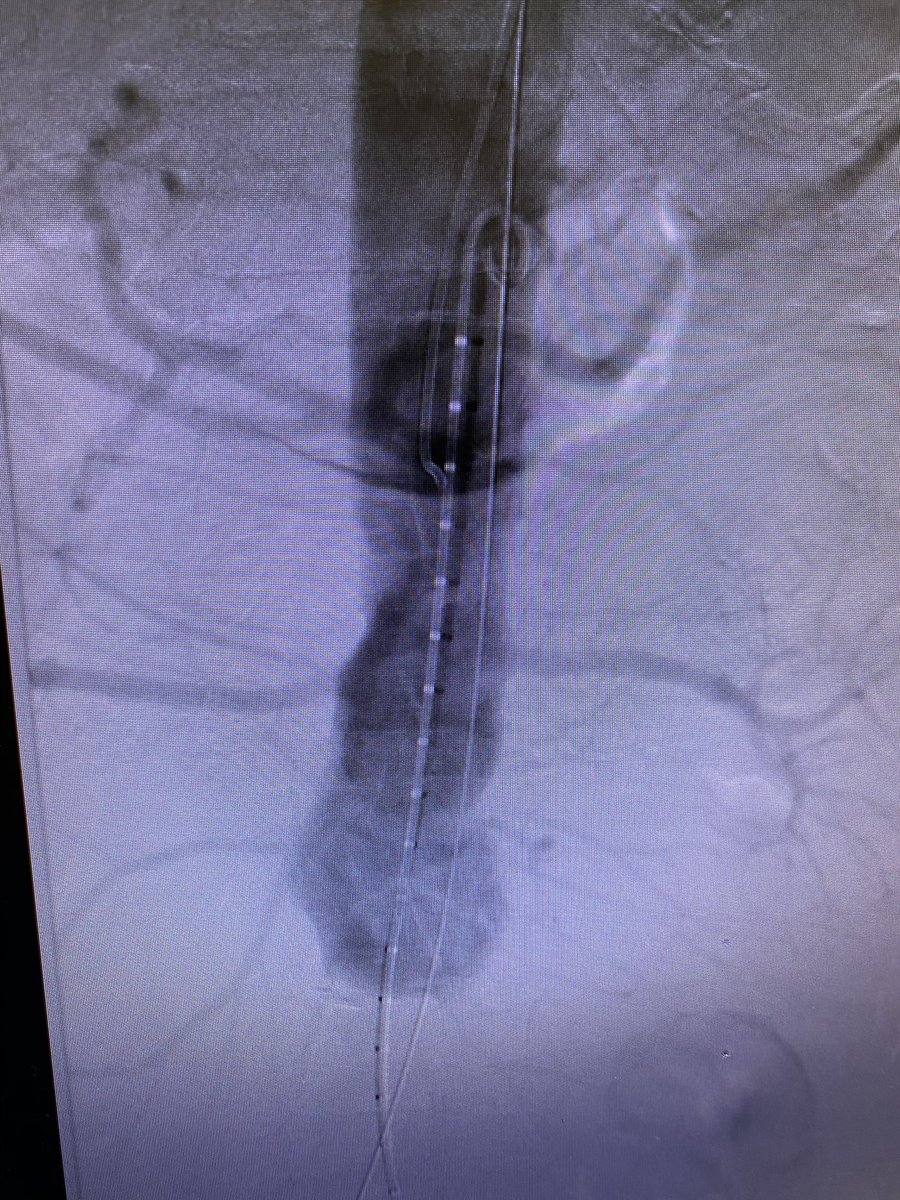

Type 4 thoracic central vein obstruction (TCVO) with arm swelling and poor fistula maturation. Superior vena cava (SVC) reconstruction may improve quality of life for venous and dialysis patients. #InterventionalRadiology #IRAD @UWRadiology @FredBertinoMD @davidsshin @SIRRFS

#FEVAR with ZFEN for 63 y/o M w/ 5.3cm juxtarenal AAA w/ hostile thrombus-lined neck ext to celiac tx'd with left brach cutdown, right fem cutdown, and left fem access:

- SMA Fen

- L Renal Fen

- R Renal Fen

- Celiac stent

w/ @michealayad3 @bolivieriMD @SIRRFS @VascularSVS